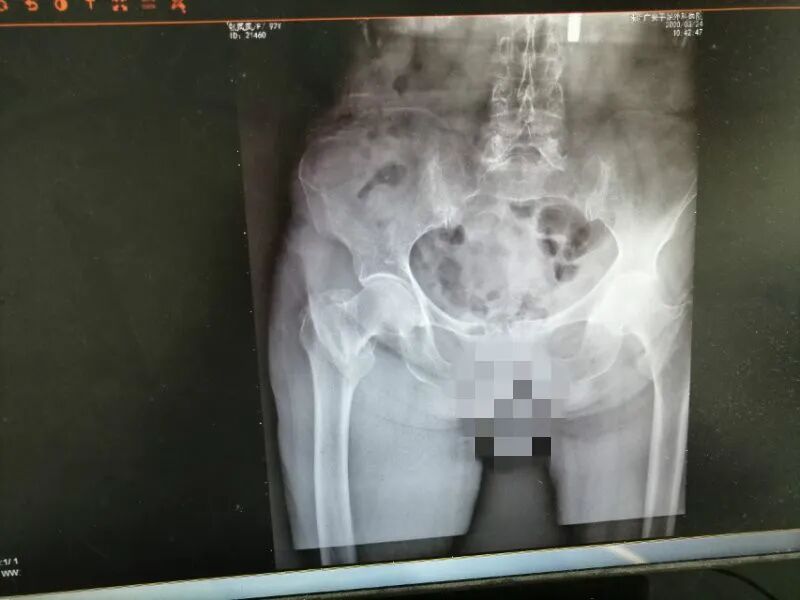

等到了第二天家里人才发现了有不妥,平日里奶奶早上会下床活动活动,今天却没看到,去奶奶房间问她才知道昨天摔跤了,对比了一下左右两边髋部发现大小不一样,右边的明显的肿胀了起来,而且活动没有之前灵活,家人忙送奶奶来珠海广安手足外科医院拍片子检查,门诊仔细检查后诊断:1、右侧股骨粗隆间骨折;2、胸12腰椎椎体陈旧性骨折;3、冠心病。收入骨科治疗。

考虑到患者年纪比较大、手术风险相对增加、术后并发症以及家属对手术担忧等问题,在谢业东主任和梁翠庆医生细心的阅片讨论,认真查体,并请示了胡寿春副院长进行会诊后,制定了完善的手术治疗计划,术前,医生耐心给家属分析患者身体情况并讲解手术方案,讨论过程所可能的风险,术后功能锻炼以及一些注意事项,经过两位主治医生一番耐心细致的讲解后,家属表示理解并相信我们的医生,决定进行手术治疗。